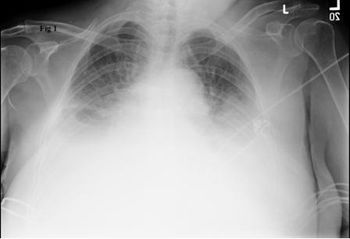

Pulmonary edema, tracheal stenosis, pulmonary embolism, pulmonary sarcoidosis, respiratory bronchiolitis interstitial lung disease, giant bullous emphysema-a close look at a variety of troublesome lung conditions.